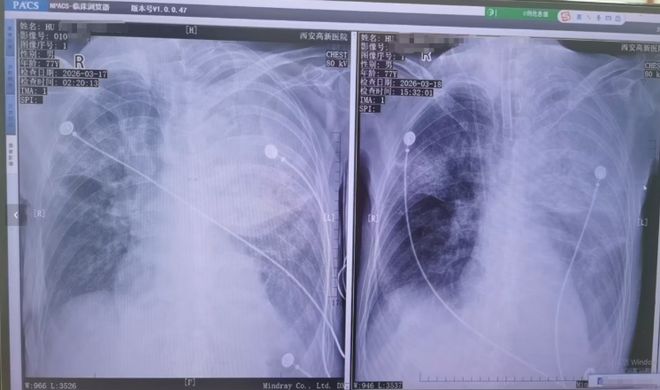

患者接受转院治疗

胡先生说,起初以为是感冒,住院治疗没有效果,还越来越严重,以至于病情危重,“整个肺部全白了”,并且出现呼吸衰竭,医院甚至下了病危通知书。3月17日,家人赶紧将父亲转院到西安高新医院抢救,到医院以后就住进了ICU。经检查,才发现是鹦鹉热衣原体感染导致的重症肺炎。胡先生提供的一份《西安高新医院诊断证明》显示,胡先生的父亲3月17日以重度肺炎入院。诊断为重症肺炎(鹦鹉热衣原体感染)I型呼吸衰竭,急性呼吸窘迫综合征,脓毒症等。

患者胸片